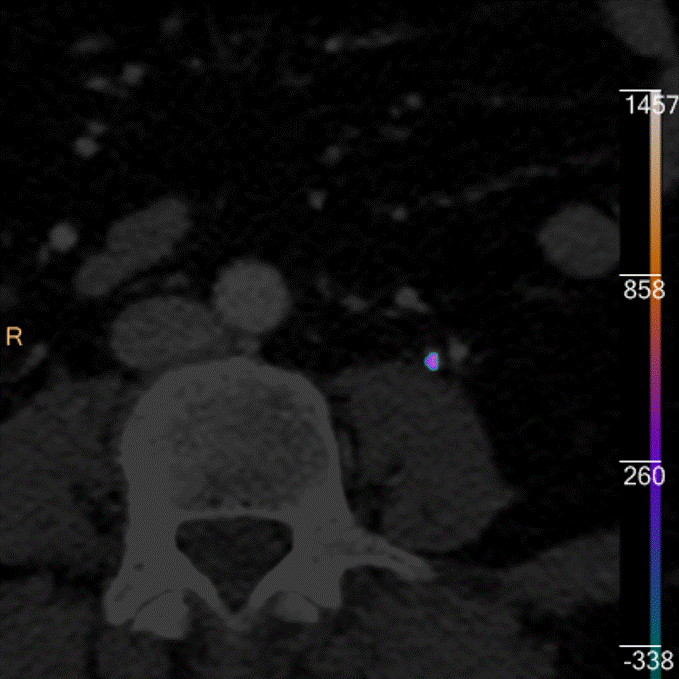

Virtual non-contrast: Stone pops out.